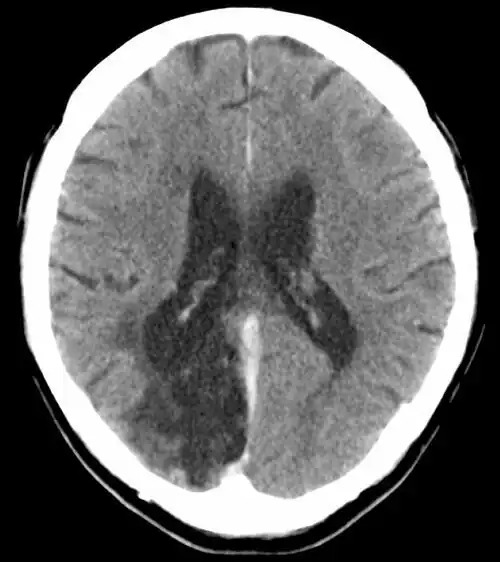

POCI (ang. posterior circulation infarct) – zawał mózgu w obszarze unaczynienia tylnego, tzn. kręgowo-podstawnego.